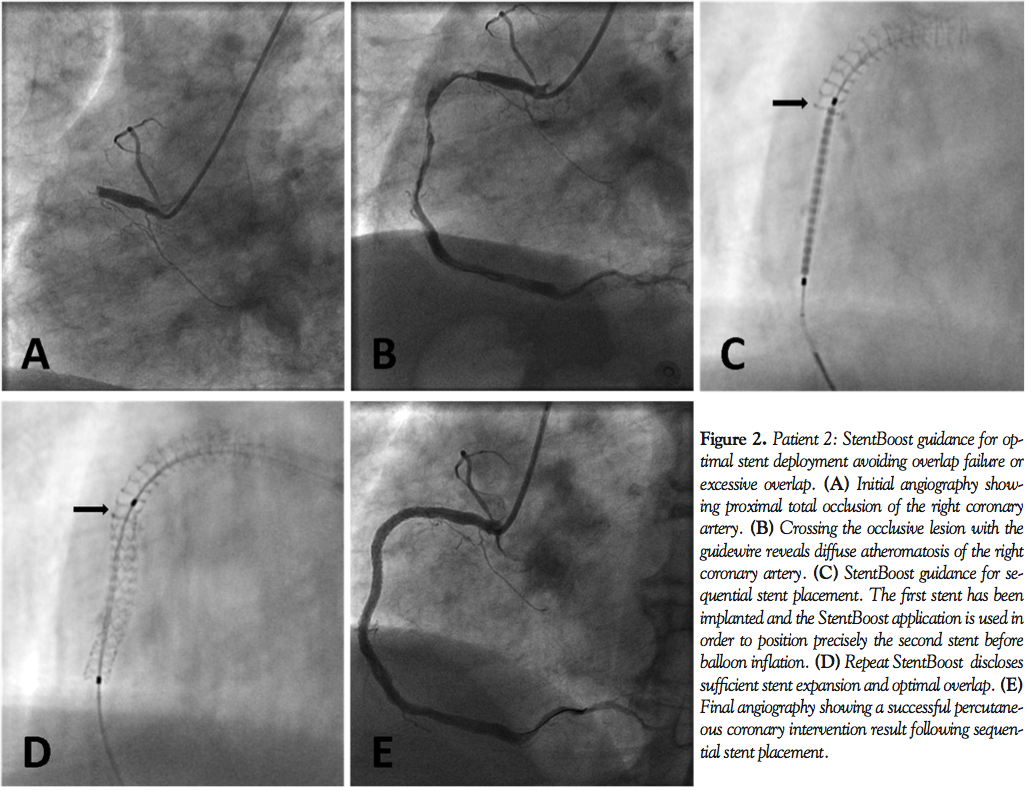

Patient 1. A 71-year-old, male smoker with a positive history of coronary artery disease was transferred to our tertiary center for catheterization due to an inferior non-ST elevation MI. Coronary angiography (CAG) disclosed a significant proximal stenosis of the right coronary artery (Figure 1A; arrow). PCI was performed and two adjacent-sequential drug eluting stents (DES), 3.5 x 18 mm and 3.5 x 10 mm, were deployed under plain fluoroscopic guidance, with visual estimation of “optimal” overlapping by the operator (Figures 1B and 1C). The result of PCI was deemed successful with no residual stenosis (Figure 1D). Subsequent imaging with the StentBoost™ technique indicated sufficient expansion of both stents but no overlap, with clear visualization of a gap between the deployed stents (Figure 1E; arrow).